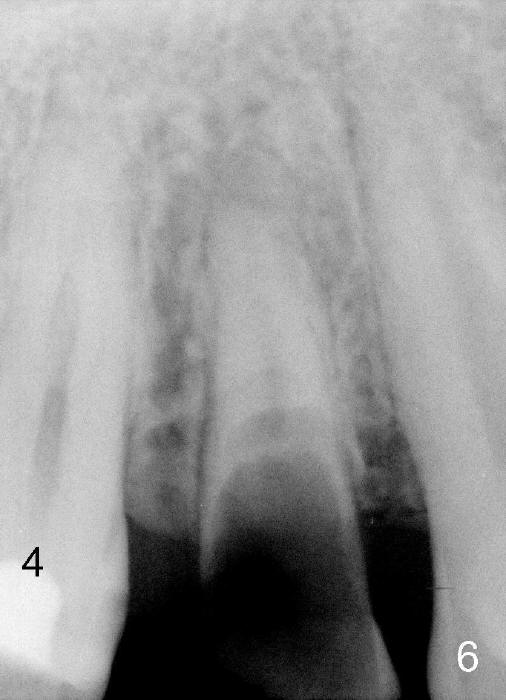

A long implant will be placed (possible 4.5x20 mm, Fig.2). A typical 1st bicuspid has 2 canals. In this case, there are most likely two roots (Fig.3): buccal (Fig.4 green dashed line) and lingual (Fig.5 pink dashed line).

The tooth #4 has special canal morphology (Fig.6). In addition to the middle main canal (Fig.7 *), there are 2 lateral finer curved canals (arrowheads). The tooth #13 has the same canal patterns.